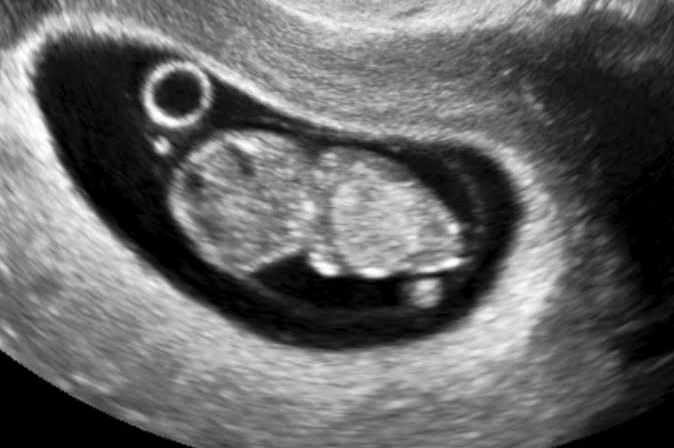

Robyn Palmeri, a sonographer at LifeChoices Family Medical Clinic, was the first to show Kayla images of her baby.

“For most women, when they come to my ultrasound room, it’s the first time they see a live image of their baby and hear the heartbeat,” said Palmeri. “When I showed Kayla her baby, she was elated. She asked if the baby was OK and when I told her the baby was OK, she was happy and peaceful.”